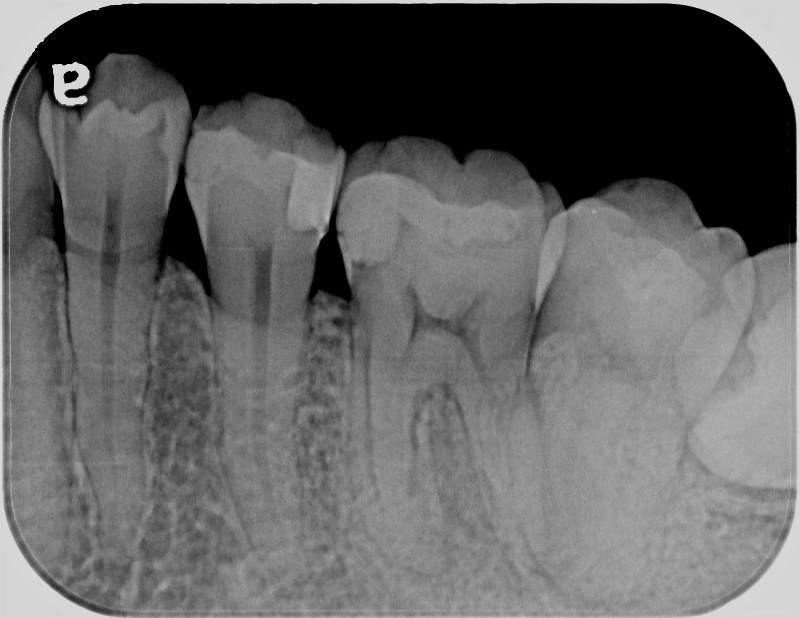

田原本町在住 30代 女性 左下第一大臼歯 精密根管治療「噛むと痛い」

術前

年齢:性別 30代:女性

主訴:噛むと痛い

診断:左下第一大臼歯 歯髄炎

治療内容:ラバーダム使用 精密根管治療

治療時間:90分×2回

担当医のコメント:2ヶ月前から痛みがひどくなり薬を飲んでも効かない急性炎症で当院を受診。

通常の処置をして麻酔後、神経を抜髄し根管治療行った症例です。

術後違和感がありましたが1ヶ月後その症状も取れ経過良好です。